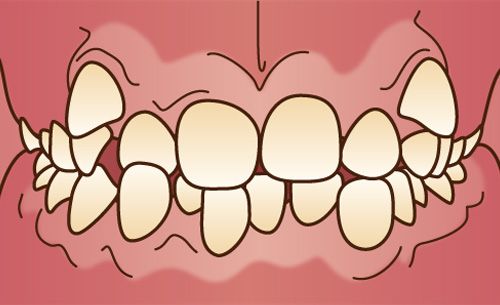

上顎の前歯が前に傾斜していたり、突き出ていたりする状態で、一般的に「出っ歯」と呼ばれています。